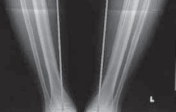

16. Intraoperative complications

1. Fracture of the medial or lateral cortex (

FIG 4A

)

2. Intra-articular extension of the osteotomy (

FIG 4B

18. Delayed postoperative

1. Patella baja

2. Nonunion or delayed union

3. Hardware failure (

FIG 4C

4. Collapse with loss of osteotomy correction (

FIG 4D–F

### FIG 4 • A. Lateral cortical breach stabilized with a three-hole 1/3 tubular plate. This was placed after the osteotomy had propagated through the lateral wall of the tibia. B. Intra-articular extension of the osteotomy that was not repaired intraoperatively, with subsequent osteotomy collapse and hardware breakage. C. Hardware failure. There is no collapse of the osteotomy, but the distal screws failed secondary to micromotion.

### FIG 4 •

(continued)

D–F. Collapse of the osteotomy with loss of correction. D. One-week postoperative image with mechanical axis at lateral tibial spine. E. Four-month postoperative image with significant osteotomy collapse (4 degrees of varus). F. Ten-month postoperative image with final osteotomy collapse into 10 degrees of varus. The patient started off with a 15-degree varus deformity.**